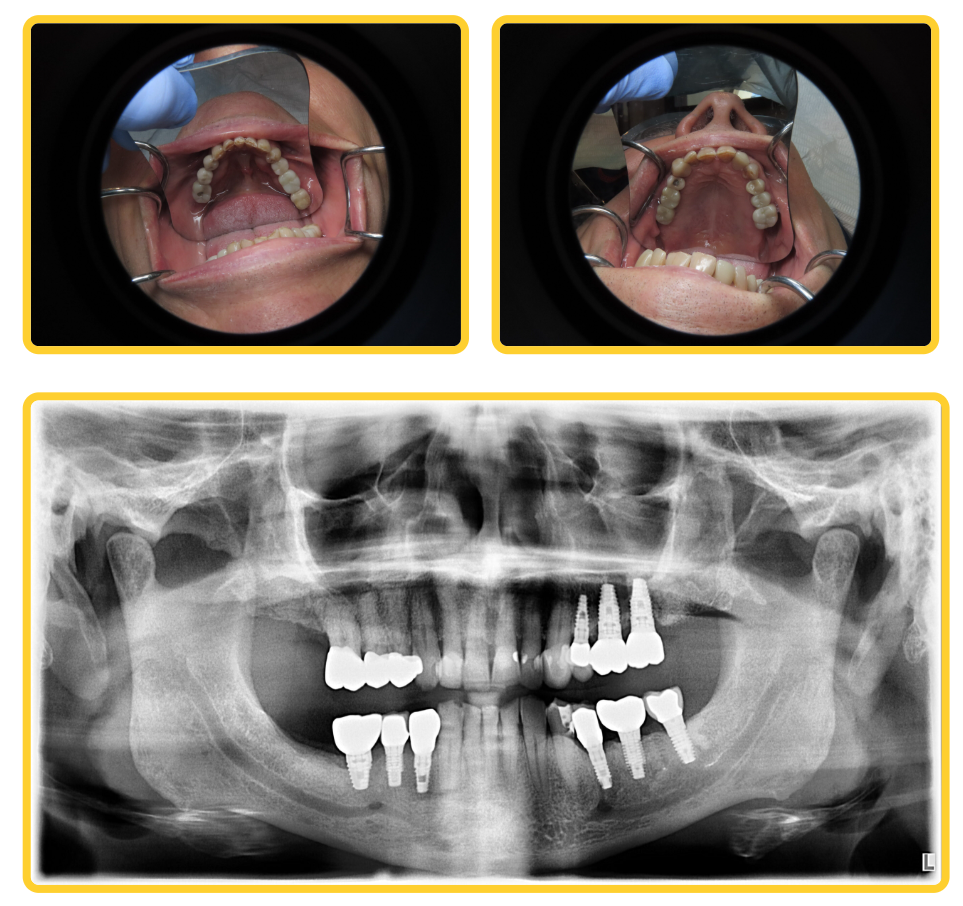

Travis came to Boston Dental Care after a diagnosis of periodontal disease and increasing looseness in several back teeth. Naturally, he worried about infection, tooth loss, and how treatment might affect his long-term oral health. Earlier, he had visited a large, heavily advertised implant center. There, he was told that all his teeth needed removal and replacement with full-arch dental implant. That recommendation alarmed him. As a result, Travis sought a second opinion and turned to Dr. Robert Thein for a more thorough evaluation.

During the consultation, Dr. Thein carefully evaluated which teeth could be saved and which could not. Although periodontal disease was present, not every tooth was failing. Instead of recommending an aggressive one-day teeth replacement procedure, Dr. Thein explained an important fact: removing healthy teeth is permanent and often unnecessary. Therefore, he recommended a conservative dental implant surgery approach. This plan focused on stabilizing oral health, preserving natural teeth, and replacing only what truly required replacement. Because of this approach, Travis avoided full dentures and unnecessary extractions.

To support long-term success, Dr. Thein developed a phased treatment plan that addressed both infection control and structural stability. First, periodontal disease was treated to reduce inflammation and protect remaining teeth. Next, only teeth with a poor prognosis were removed. Dr. Thein then placed dental implants selectively, based on bone quality and bite forces. When bone volume proved insufficient, he performed bone grafting or sinus grafting where needed. Later, each implant received a custom restoration designed to improve comfort, function, and bite balance. In complex implant cases, this level of planning makes a measurable difference in outcomes.

Phase 3: Strategic Dental Implant Placement

Rather than placing implants broadly, Dr. Thein positioned them only where they were truly needed. He planned each implant based on anatomy, bone density, and the final restoration.

Phase 4: Bone Grafting and Sinus Grafting When Needed

Years of periodontal disease can reduce bone volume. When necessary, Dr. Thein rebuilt that foundation with bone grafting and sinus grafting. He performed these procedures selectively to support implant longevity.